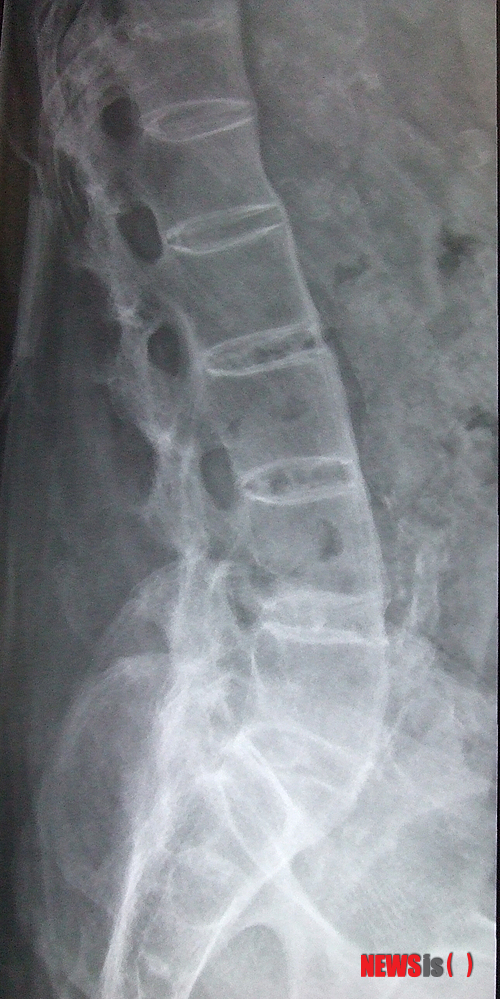

강직성척추염은 척추 디스크와 척추 뼈가 만성 염증성 관절염 탓에 서로 붙어 대나무처럼 굳는 질환이다. 원인은 아직 밝혀지지 않았지만, HLA-B27이라는 유전자와 많은 관련이 있다고 알려져 있다. 염증은 엉덩이 관절에서 시작해 허리를 거쳐 목까지 진행되며 결국, 척추 전체가 변형돼 목이나 허리 척추 관절이 굳어 움직이지 않게 된다.